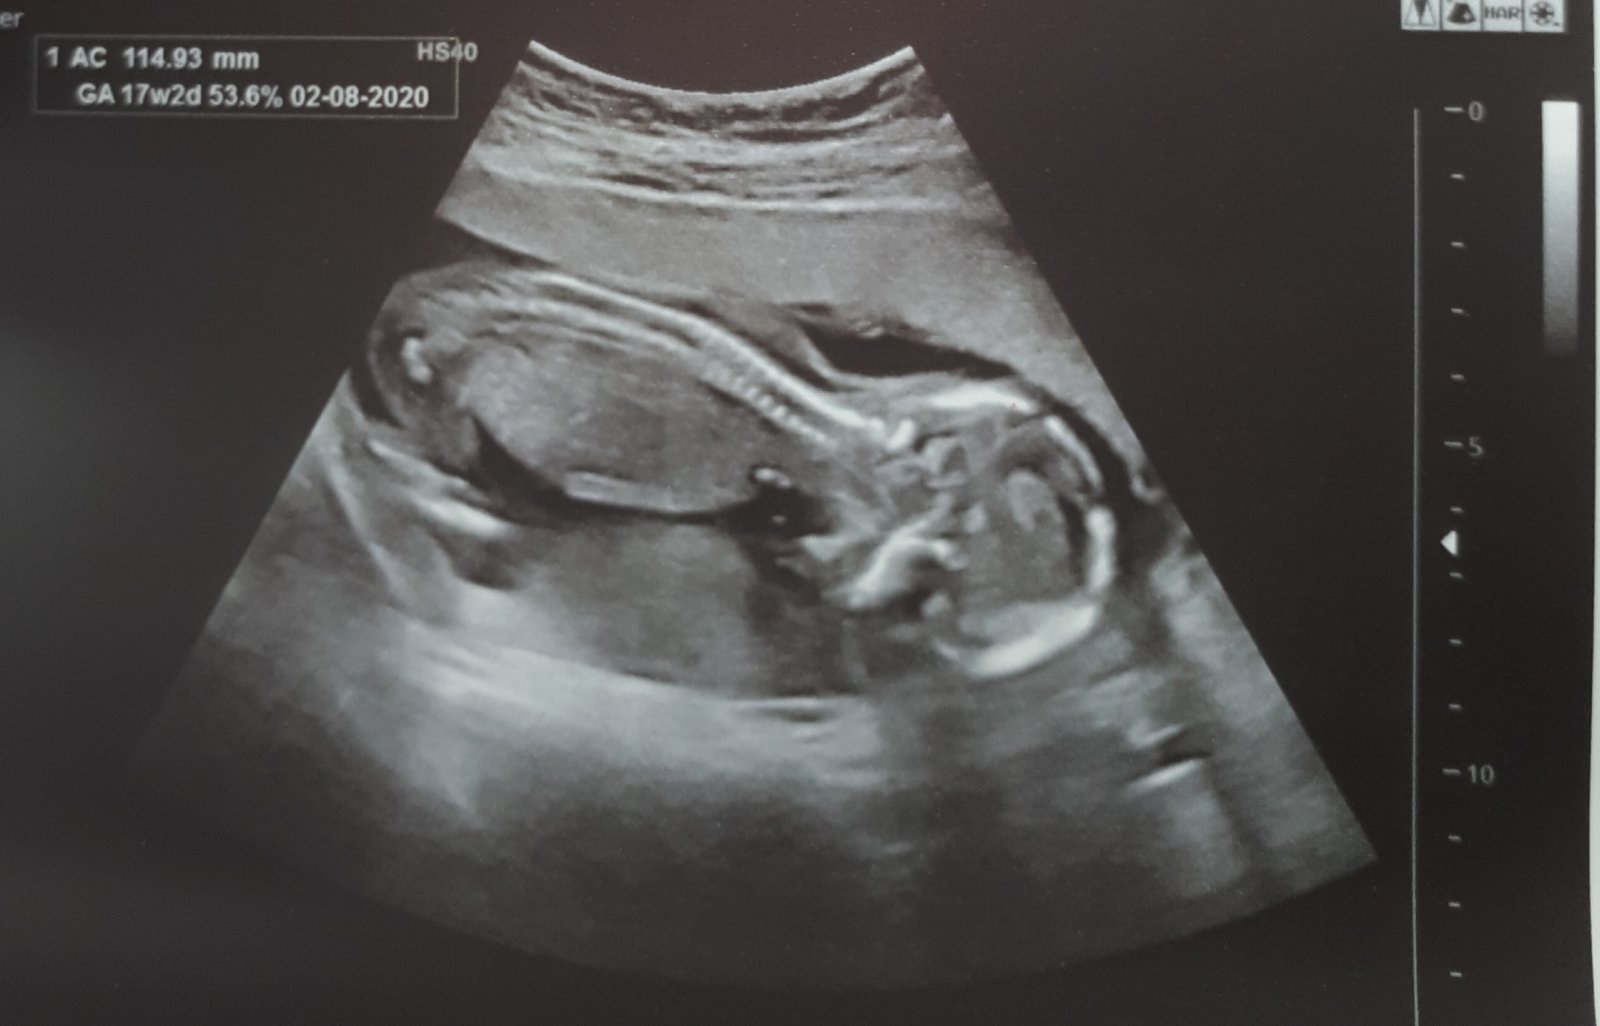

25. 2. 2020

- dnes 17+1tt a kontrolní UTZ, vše v pořádku, srdíčko 🧡 141 tepů, miminko se má čile k světu, polyp na čípku se zmenšuje

- moje váha 72 kg, přírůstek +4 kg 😞

- odebrána krev na Triple testy